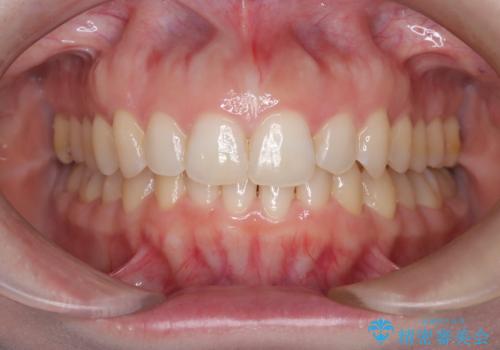

【インビザライン】前歯の凸凹を治したい。

- 前歯の凸凹を主訴に来院されました。

深い噛み合わせも同時に治療を行う計画を立て、インビザラインを使用して歯並びの改善を行うことができました。

叢生改善のために遠心移動とIPRを行なっています。